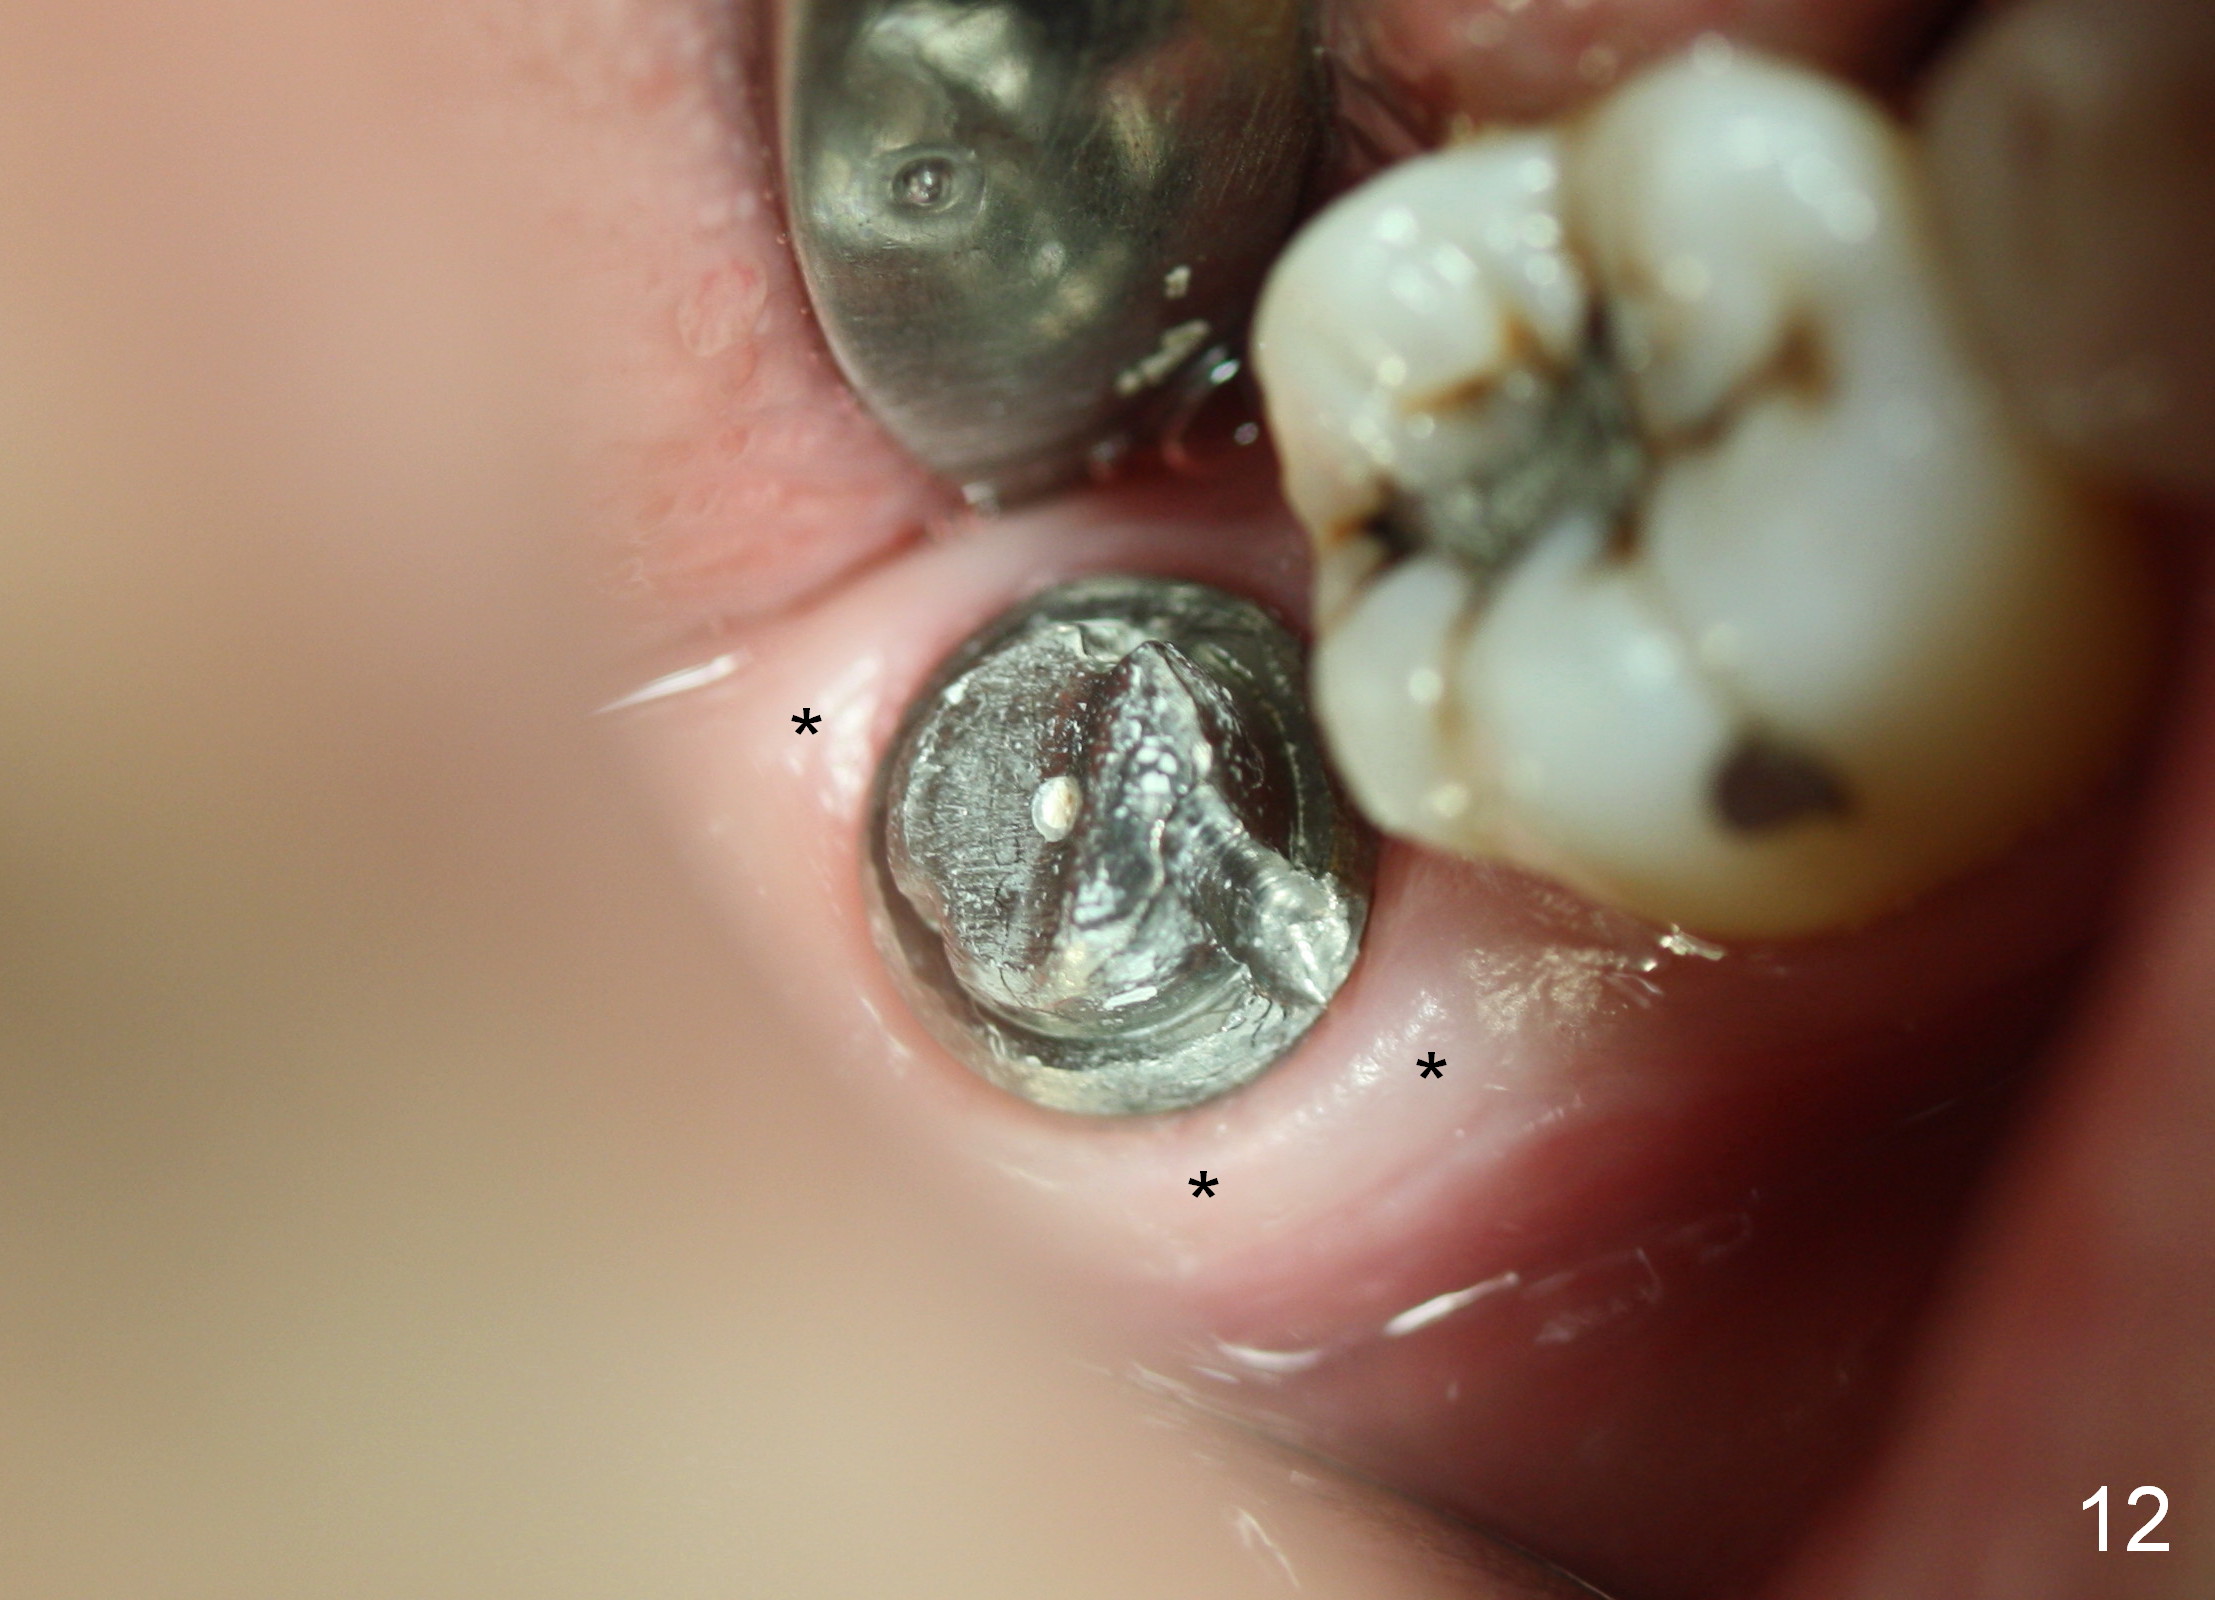

The tooth #31 of a 38-year-old lady has endo perio disease (Fig.1). Due to the large periapical lesion, there will be no solid (new) bone available for primary stability of an immediate implant (Fig.2: 7x17 mm). Yellow dashed line represents the upper border of the Inferior Alveolar Canal (IAC). Infiltration anesthesia is administered first. The mesiodistal widths of the root of the extracted tooth are 10 and 7 mm at the coronal and apical ends, respectively; the buccolingual ones 7 and 5 mm; the length 17 mm (Fig.3). The socket appears much larger than the root (Fig.4). To prevent paresthesia, no drills are used. Instead, a series of tap drills (6,7,8x17 mm) are sequentially inserted into the socket. The largest tap (Fig.5 T; 8x17 mm) binds to the socket securely with separation from IAC. Block anesthesia has to be administered before removal of the tap. A tapered implant (8x17 mm) is placed with insertion torque greater than 60 Ncm (Fig.6 I); allograft mixed with Osteogen is placed around the implant (*). Collagen dressing covers the opening of the remaining socket. The wound is protected with perio dressing, which is partially secured by an abutment (A in Fig.6). No paresthesia is reported by the patient a few hours postop.